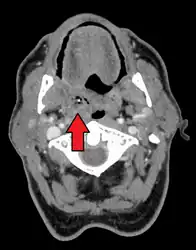

Diagnosis is usually based on the symptoms.[1] Medical imaging may be done to rule out complications.[1] Medical imaging may include CT scan, MRI, or ultrasound is also useful in diagnosis.[1]

Peritonsillar abscess on the person's right as seen on CT imaging

Peritonsillar abscess